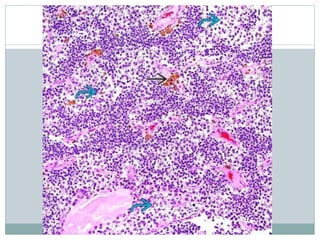

• #13 This case of ES features a more prominent lobulated pattern of growth with large nests and sheets of clear tumor cells separated by thickened fibrocollagenous septa .

• #15 Coagulative necrosis is common in ES and is often geographic in distribution. A common finding is the presence of perivascular tumor cell preservation ("peritheliomatous growth") with degeneration and death of surrounding cells.